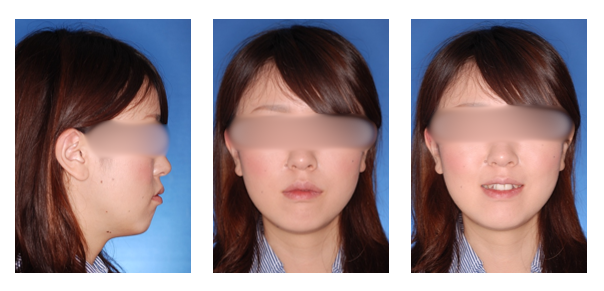

上顎前突の症例

初診時

治療終了時

治療終了時から2年経過時(保定開始時から2年経過時)

初診

治療終了時

治療終了後から2年経過時

(保定開始時から2年経過時)

| 年齢・性別 |

20代 女性 |

| 主訴 |

前歯が出ているのを治したい。 |

| 治療について |

上は前歯をかなり下げるために小臼歯、更に大臼歯を抜歯、下はガタガタを治すため、小臼歯の抜歯を行いました。 |

| 治療期間 |

2年 |

| 治療費用 |

1,310,100(検査料と診断料、全ての調整料を含みます) |

| 治療に用いた主な装置 |

マルチブラケット装置(上顎舌側、下顎唇側の装置)、歯科矯正用アンカースクリュー |

| 抜歯部位 |

上顎両側第一小臼歯、第二大臼歯、下顎両側第二小臼歯、第三大臼歯 |

| 通院回数 |

21回 |